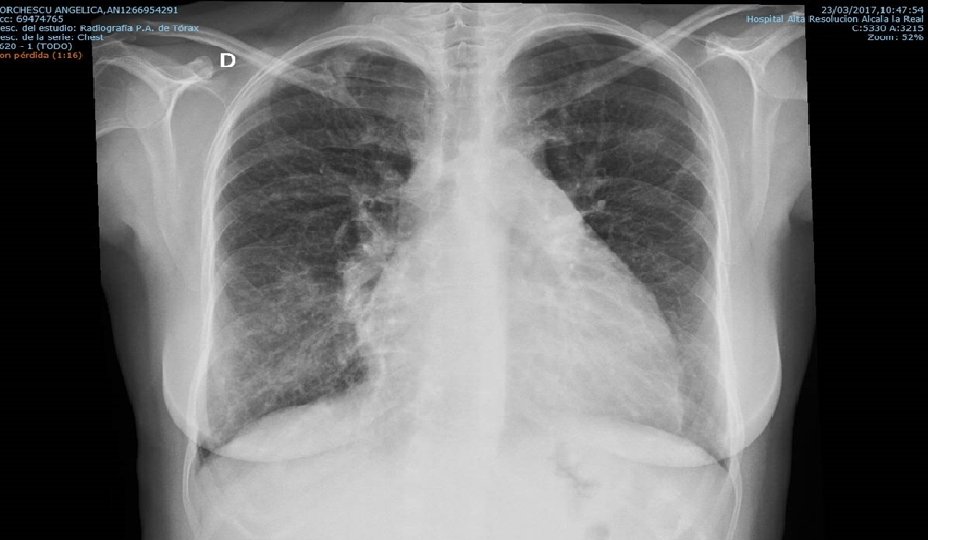

• Mujer. 44 años. Natural de Rumanía • TEP + TVP MID (2013). Fibrinolisis → HBPM → Acenocumarol+ AAS • Sd. Antifosfolípido Primario. ANA 1/640. Homogéneo • Heterocigota mutación Factor XII.

• 04. 2014: Palpitaciones, mareo. Fiebre prolongada. ↓ peso Disnea súbita. • BK: presencia BAAR. • TBC PULMONAR • TEP • Defectos replección arterias segmentarias LSD, LMD, LII. Cardiomegalia a expensascavidades derechas. Dilatación v. suprahepaticas. Reflujo contraste

• 12. 2015: • Disnea. Anemia. Menorrragias • EF: taquipnea. EY (+). TA: 107/65. ACR: Ø • LAB: BNP: 496. Hb: 6 gr/d. L • RMN: Leiomiomas • ECOCARDIO: PAPs: 55. VD dilatado. FE limítrofe. • angio. TAC: • • No signos TEP No cavitaciones (TBC) Vidrio deslustrado parcheado Cardiomegalia derecha. ↑ tamaño art. pulmonar • TRATAMIENTO: • Histerectomía • Acenocumarol • Bosentan + Sildenafilo (prescrito por U. Enf. Autoinmunes)

• 2016 -2017. • Disnea esfuerzo. Hb: 18 gr/d. L. • PFR: • CVF: 80%. VEF 1: 58%. VEF 1/CVF: 77%. DLCO: 84%. • ECOCARDIOGRAFÍA: • Aplanamiento septal. VD dilatado con FE subjetiva severamente deprimida. TAPSE: 14 mm. Dilatación AD. VCI dilatada (30 mm) con colapso inspiratorio <50%. PAPs~82 mm Hg. Posible foramen ovale permeable • GAMMAGRAFIA V/Q: • Alta probabilidad EP